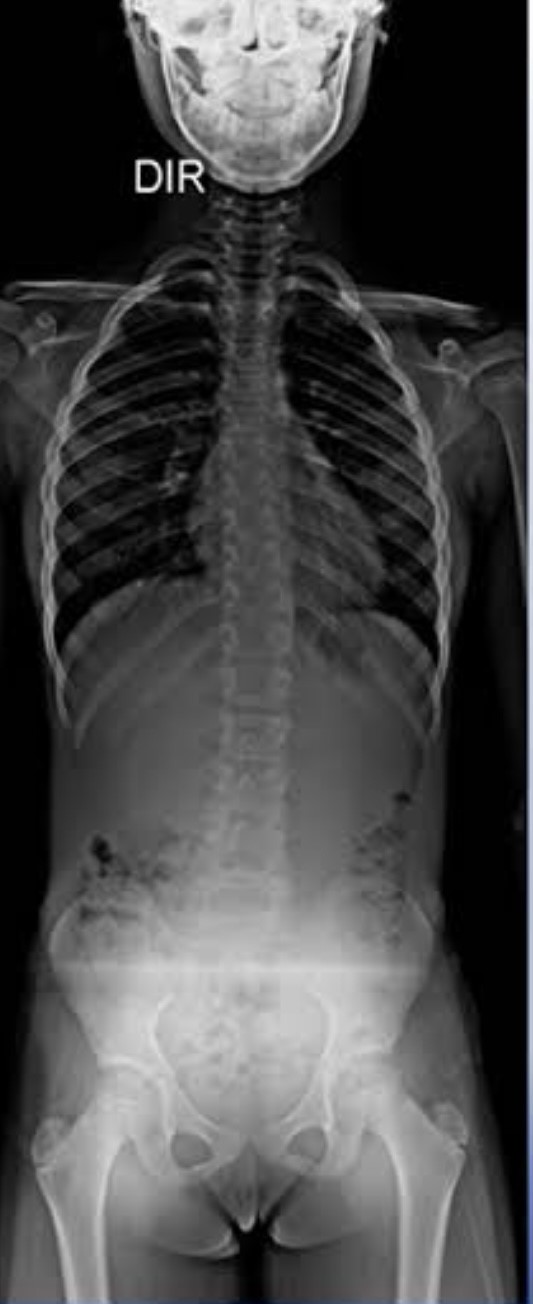

- Radiografia panorâmica da coluna normal sem escoliose

- Radiografia panorâmica da coluna com escoliose

Radiografia panorâmica da coluna